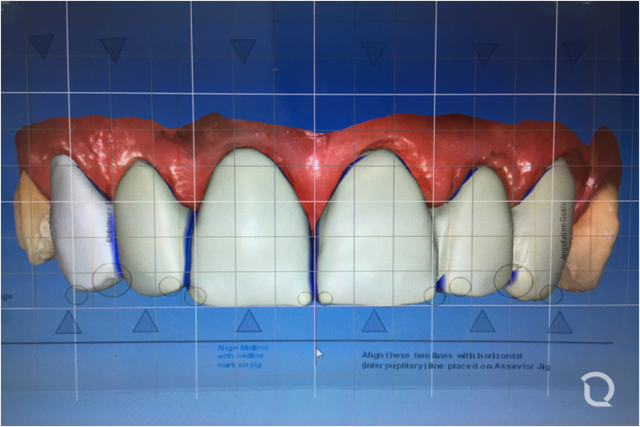

PROCERA de Nobel Biocare, con tecnología CAD/CAM de punta, se desarrollo para elaborar restauraciones individualizadas, utilizando última tecnología de escaneo y diseño asistido por computador (CAD), combinado con una manufactura industrial (CAM), muestran grandes ventajas clínicas sobre los otros sistemas, ya sean asistidos o no por un computador. Las coronas totalmente cerámicas en alumina (Procera AllCeram) fueron introducidas en 1991

El comienzo de un nuevo siglo, después de haberse asentado clínicamente –tras una década de uso– la Radiología Digital y expandirse tímidamente el CAD-CAM Dental, no solamente con CEREC y PROCERA, sino con algunos desarrollos posteriores de otros fabricantes (Lava-3M-Espe, Everest-Kavo, Digident-Girrbach, Degussa, GC, Bego,), es el inicio de un exponencial crecimiento de estos sistemas de diseño (CAD) y fabricación (CAM) asistidas por ordenador, para todo el sector dental.